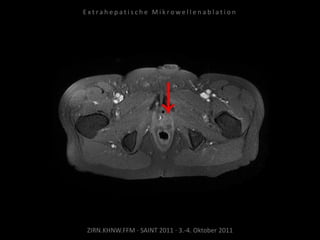

Bildgebung vor MWA:

MRT 03.02.2010

Situation:

Bei Z.n. Prostataresektion + Radiatio

+ Seed nun Rezidiv in kritischer

Position.

Ablation am 25.03.2010:

1 Nadelposition, 45 W, 7 Min.

Während der Ablation werden

Harnleiter, Harnblase und Rektum

zwecks Hitzeableitung gespült zur

Vermeidung thermischer Schäden.